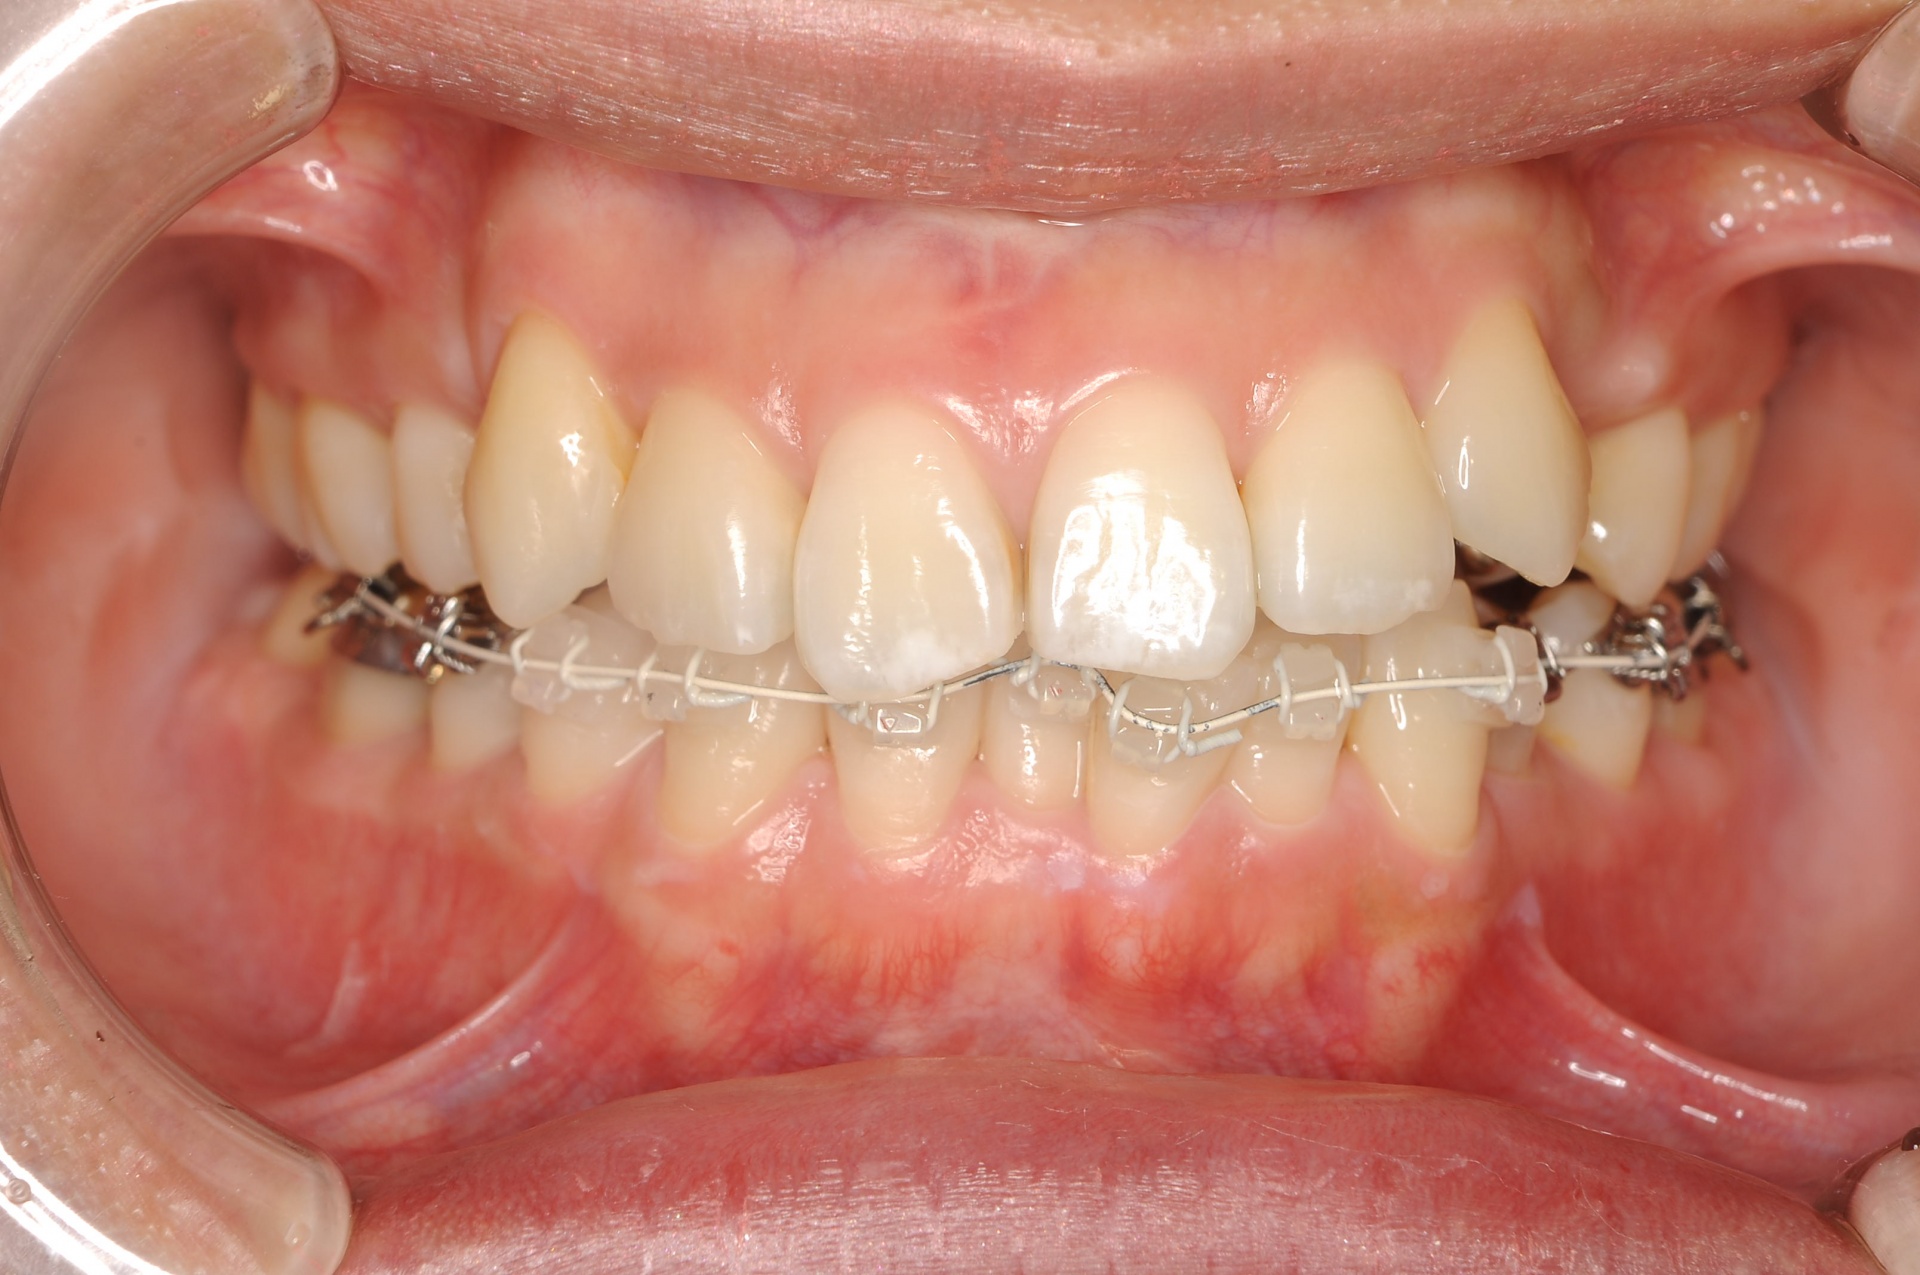

治療中

見えない装置(裏側矯正)を希望されましたので、上顎は裏側に装置をつけて、下顎はセラミックの白い装置としました。上顎両側犬歯を小臼歯の抜歯したスペースへ移動させました。下顎は非抜歯で叢生を改善しました。